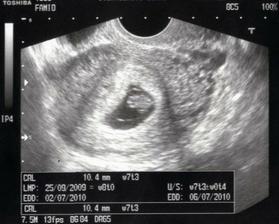

20.11.2009,8+0tt

Kontola u dr. dopadla na 1 :o) .Miminko krásně roste, AS +, velikostně dle UTZ 7+3tt.